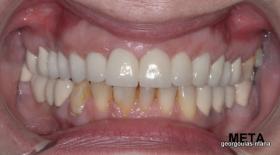

ΟΛΙΚΗ ΑΠΟΚΑΤΑΣΤΑΣΗ ΑΝΩ ΓΝΑΘΟΥ

Η ασθενής ήταν δυσαρεστημένη από την εμφάνιση των άνω δοντιών της. Ήθελε τα δόντια της να αποκτήσουν ομοιόμορφο, πιο λευκό χρώμα κ να αποκτήσει ένα πιο αρμονικό χαμόγελο με φυσική εμφάνιση. Λόγω των εκτεταμένων εμφράξεων σύνθετης ρητίνης στα πρόσθια δόντια, των εμφράξεων αμαλγάματος στα πίσω αριστερά δόντια αλλά και της υπάρχουσας γέφυρας στα πίσω δεξιά δόντια, και σε συνδυασμό με την επιθυμία της ασθενούς για φυσικό αποτέλεσμα αποφασίστηκε η τοποθέτηση ολοκεραμικών στεφανών στα δόντια της άνω γνάθου. Στη θέση του δεύτερου προγομφίου δεξιά τοποθετήθηκε εμφύτευμα. Πραγματοποιήθηκε περιοδοντική θεραπεία, ενδοδοντικές θεραπείες (απονευρώσεις) κ τοποθετήθηκαν ενδορριζικοί άξονες υαλονημάτων  όπου κρίθηκε απαραίτητο. Σε όλη τη διάρκεια της θεραπείας η ασθενής ήταν καλυμμένη αισθητικά κ λειτουργικά με προσωρινές αποκαταστάσεις.